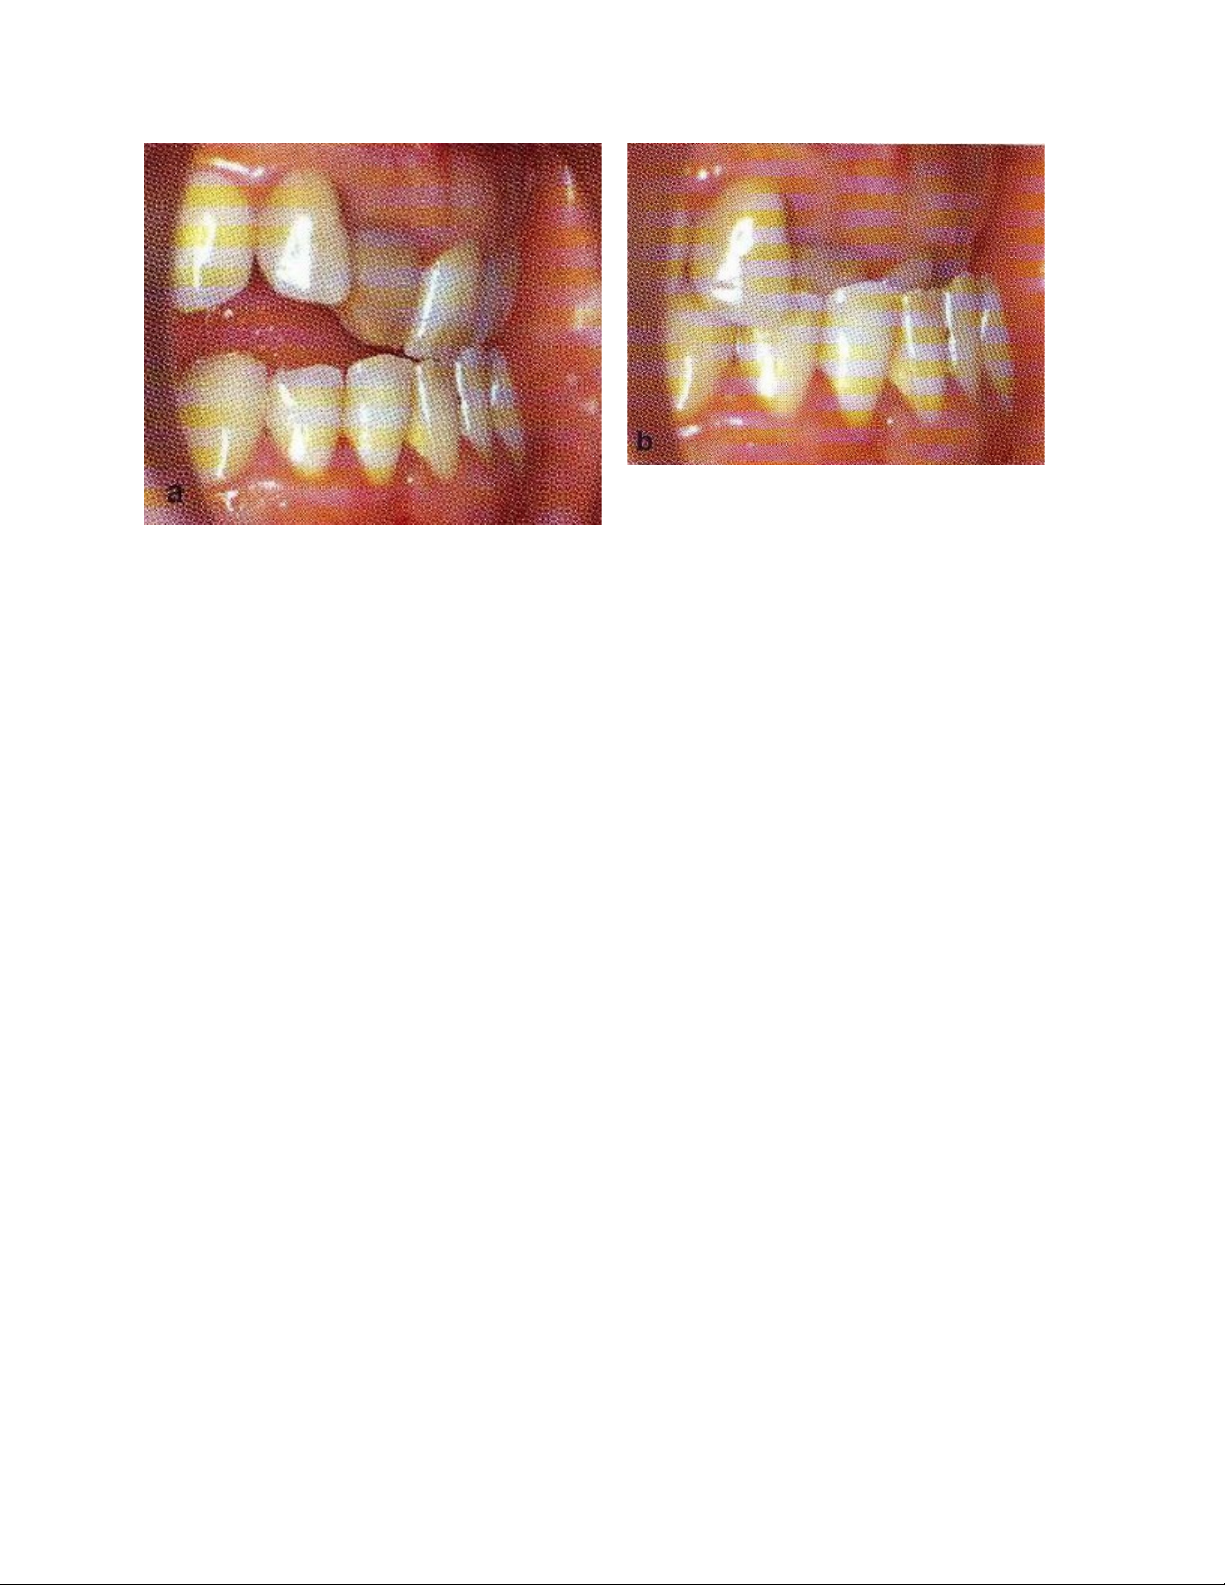

Hình : a. Chạm răng cửa trong hành trình ngậm miệng, b. tư thế lồng múi

Nếu sự trượt gây rối loạn chức năng khớp thái dương hàm hoặc làm trầm

trọng các tổn thương nha chu ở các răng liên quan cần phải điều chỉnh khớp cắn.

Mục đích điều trị nhằm giảm các điểm chạm sớm, loại bỏ hoặc giảm các dốc trượt.

Phương pháp điều trị thay đổi theo mức độ trượt, mức độ trượt phụ thuộc

vào độ cắn phủ của răng ngược. Khi độ cắn phủ quá lớn, chênh lệch giữa khớp cắn

chạm múi tối đa và hành trình ngậm miệng rất lớn, do vậy chỉ định thay đổi khớp

cắn chạm múi tối đa bằng cách thay đổi tương quan cắn bằng phương pháp chỉnh

răng, phẫu thuật và hoặc hàm giả. Ngược lại khi dốc trượt thấp, điều chỉnh cắn có

thể được chỉ định bằng cách giảm sự trượt không thay đổi khớp cắn chạm múi tối

đa.